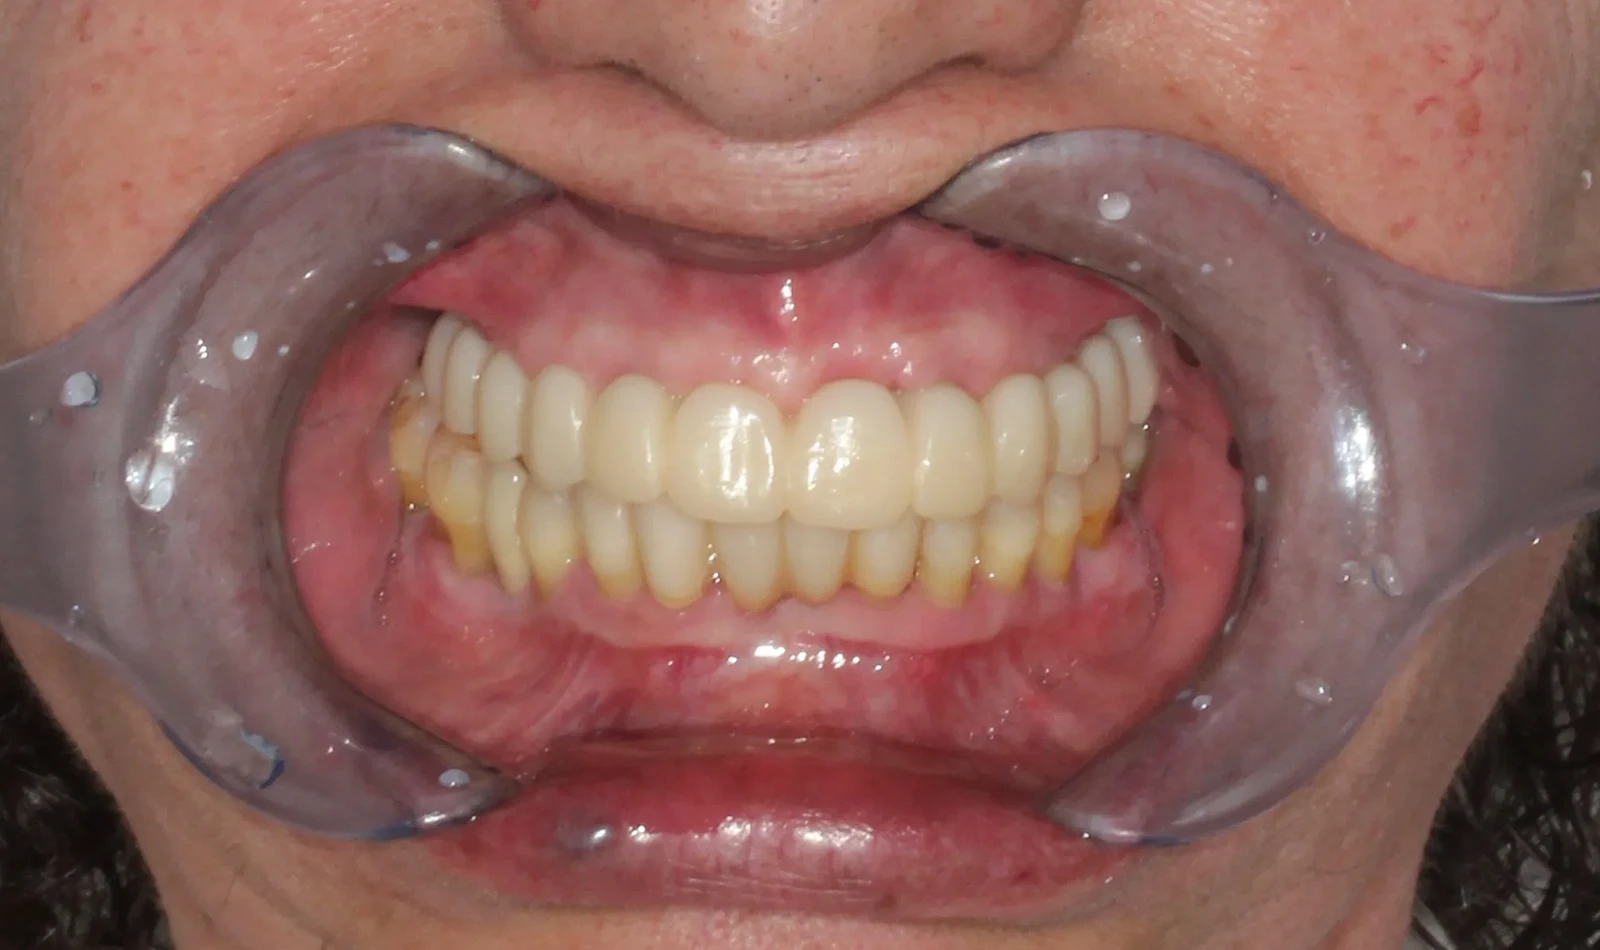

De 61 años nos visita con dientes dañados por caries y una prótesis antigua que ya no podía utilizar. Gracias a la planificación digital y la cirugía guiada, realizamos las extracciones y colocamos implantes con una prótesis fija el mismo día. Recuperó su sonrisa y la confianza de inmediato.